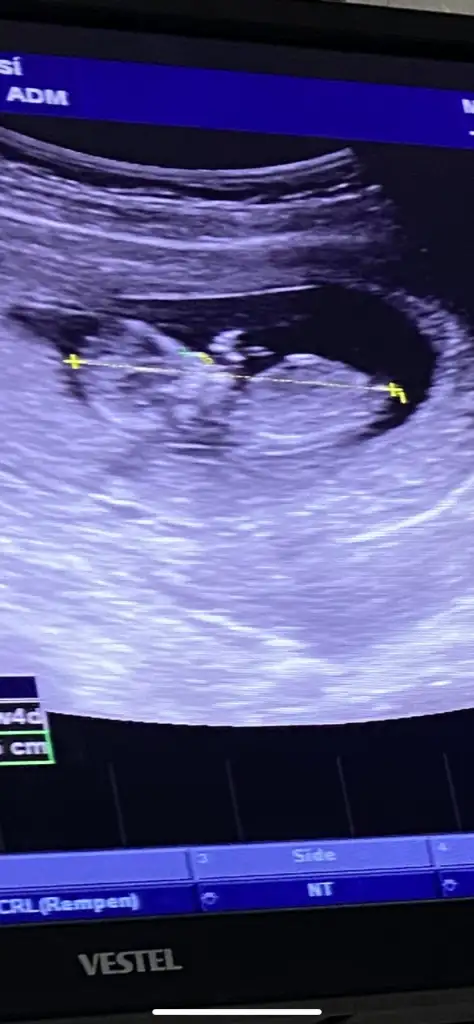

13 haftalık karından çekildiSelam Kızlarbir çok kişi gruplardan beni bilir. Yine yetiştim imdatlara

Çoook uzun bir süre araştırma okuma yaptıktan sonra sizlere bu başlığı açtım çevremde tüm gebelere de denedim. Bunun sırrını çözen İnstagramda (isim vermeyim) işi ticarete dökmüş bile.Nub, Ramzi,Çin Rus Japon Takvimleri, Yüzük Yöntemi bir çok şey size sayabilirim.

5 ve 14. haftaya kadar olan ultrason fotolarınızı paylaşın. Vajinadan mı yoksa karından mı çekildiğini ve kaç haftalık olduğunu da mutlaka belirtin.

Not: Tahmin yaptığım anneler cinsiyet öğrendikten sonra lütfen bana geri dönüş yapın